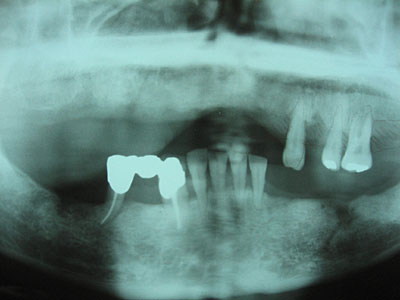

左下奥歯のインプラントの手術

患者さん:40代女性

左下奥歯のインプラントの手術を行いました。右下奥歯は以前にしたものです。

術前

最初見たときは顎の骨も薄く神経までも近く大変そうだと思いました。

術前レントゲン撮影

術中

神経を傷つけないようにレントゲン写真を撮りながら慎重にドリリングしました。

術後

少し短めのインプラントを埋めることにしました。

術後レントゲン撮影

特に問題なく埋入することができてよかったと思います。